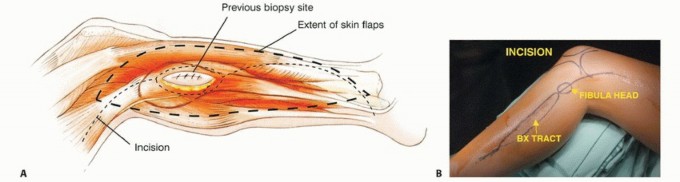

الخزعة (Biopsy)

بعد تحديد موقع الورم وحجمه بواسطة التصوير، تُعد الخزعة ضرورية لتأكيد التشخيص النسيجي للورم (نوعه ودرجته). يمكن أن تكون الخزعة بالإبرة أو خزعة مفتوحة. يتم التخطيط لموقع الخزعة بعناية لضمان إزالتها بالكامل مع الورم أثناء الجراحة النهائية. يحرص الأستاذ الدكتور محمد هطيف على إجراء الخزعة بأقل قدر ممكن من التدخل لتقليل خطر انتشار الخلايا السرطانية.

التحضير لجراحة استئصال ورم الشظية

يتطلب التحضير لجراحة استئصال ورم الشظية تخطيطًا دقيقًا لضمان أفضل النتائج وتقليل المضاعفات. يحرص الأستاذ الدكتور محمد هطيف وفريقه على إعداد المريض بشكل شامل قبل الجراحة.

وضعية المريض

يُستخدم وضع شبه الاستلقاء (رفع الجانب الذي سيتم إجراء الجراحة عليه بزاوية 45 درجة) للسماح بالوصول السهل إلى الحجرات الأمامية والجانبية، وكذلك للسماح بتشريح المساحة المأبضية. يتم تضمين الطرف بأكمله، من الرباط الأربي إلى القدم، في الحقل المعقم. هذا يسمح بتقييم نبضات القدم البعيدة وتنفيذ بتر فوق الركبة إذا لزم الأمر، على الرغم من أن هذا نادر الحدوث بفضل التقنيات الحديثة.

الشق الجراحي (القطع الجراحي)

يُستخدم "الشق الشظوي النفعي" (utilitarian fibular incision)، والذي يسمح بكشف واستئصال الأورام في جميع مستويات الشظية. يمتد هذا الشق من العضلة ذات الرأسين فوق مفصل الركبة، فوق الجزء الأوسط من الشظية، إلى الأمام باتجاه قمة الظنبوب، ثم ينحني خلفيًا وبعيدًا إلى الكاحل. يسمح هذا بتطوير سدائل جلدية عضلية أمامية وخلفية كبيرة.